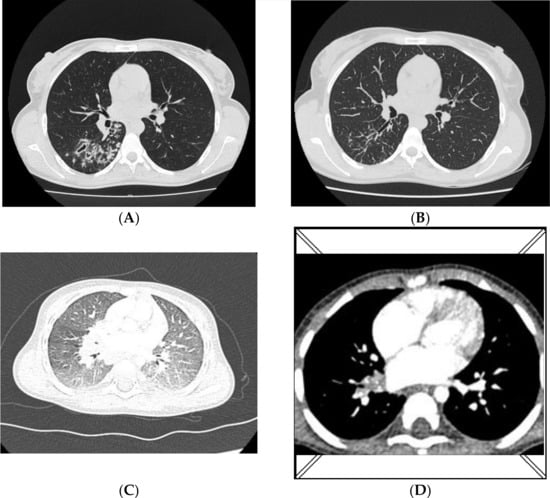

In January 2020, a 27-year-old woman with symptoms of tuberculosis visited a pulmonology clinic. For 2 months, she had a cough with mild haemoptysis and fever. A sputum smear was positive for mycobacteria (Acid Fast Bacilli, AFB+++), and the treatment was initiated according to the following regimen: rifampicin, isoniazid, ethambutol, and pyrazinamide. No improvement was achieved after 2 months of therapy, and an X-ray of the lungs on 24 March 2020 revealed patchy and nodular infiltrations localized in the right lung. The strain isolated from the sputum was identified as XDR-MTB, spoligotype Beijing 265. All molecular and biochemical tests were performed in the National Tuberculosis and Lung Diseases Research Institute in Warsaw, Poland. According to the drug-resistance phenotype determined on the liquid medium, treatment was introduced for drugs to which the strain was sensitive: linezolid, cycloserine, ethambutol, levofloxacin and ethionamide. The patient was still profusely positive for mycobacteria (AFB++). A bronchial secretion was collected on 1 April 2020 and the XDR strain, Beijing 265 genotype, was cultured again. Treatment was continued, but levofloxacin was substituted with moxifloxacin. A chest CT performed on 3 June 2020 revealed the presence of diffuse nodular lesions localized in the right lung (Figure 1A). Therapy with ethambutol was discontinued due to ophthalmic problems, while linezolid and ethionamide were discontinued because of sensory polyneuropathy. Follow-up tests for AFB (culture in solid and liquid media and detection of DNA directly in the clinical specimen) were negative in June 2020. After 6 months of antibiotic treatment, a CT scan revealed the partial regression of lesions (Figure 1B). The patient’s clinical status improved and treatment with bedaquiline, moxifloxacin, and cycloserine was finally sustained.

Figure 1.

Chest CT A/B—mother; (A)—nodular lesions in the right lung (3 June 2020); (B)—regression of lesions (5 November 2020); C/D—infant; (C)—ground-glass opacities with some consolidations localized in both lungs (12 June 2020); (D)—regression of lesions, numerous calcifications in the nodes of the right hilum and subcarinal nodes (5 October 2020).